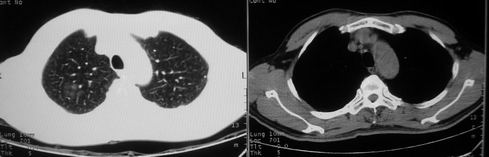

男,62岁,咳血两天。无其他不适。

像多个结节聚集在一起的病变,且密度较淡  首先考虑为结核吧  建议密切复查

片状磨玻璃影,考虑肺泡出血可能性大,其他不排除,建议hrct

片状磨玻璃影,考虑肺泡出血可能性大,不排除tb

病灶呈“磨玻璃影”,较薄,周围无卫星灶,很难一口说是肺结核,建议积极治疗后,短期复查!(支持考虑:肺泡出血!)

右肺上叶可见多发磨玻璃状影,符合肺泡内出血表现,严格意义上讲应该是肺泡内积血。引起出血的原因很多,不一定非得结核所致。